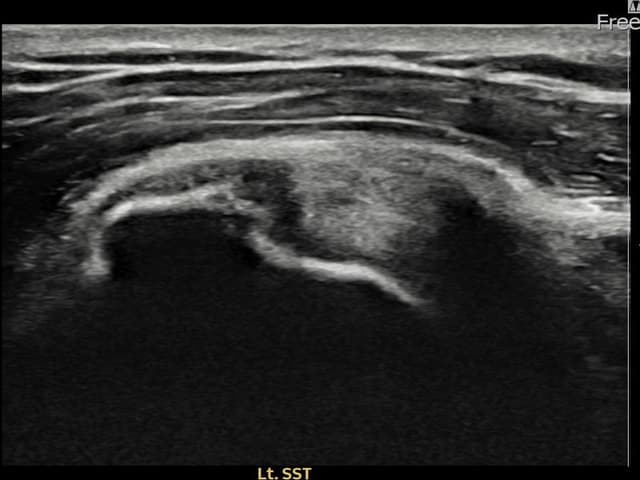

左侧 冈上肌腱 石灰化肌腱炎

9mm × 7mm